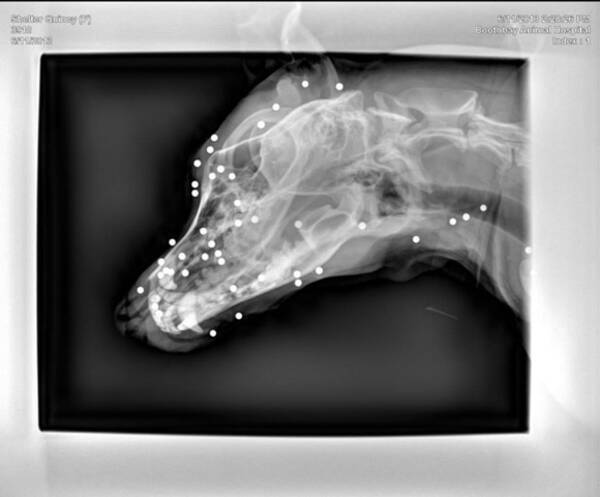

残酷 体中にbb弾を受けた犬のレントゲン写真に怒りの声 なぜだ 犯人を捕まえて牢屋にぶち込め 2013年6月17日 エキサイトニュース